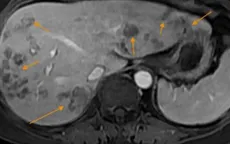

VTV.vn - Thói quen ăn gỏi cá, rau sống khiến anh L.T.N., nhiễm sán lá gan lớn, dẫn đến nhiều ổ tổn thương khu trú ở gan phải.